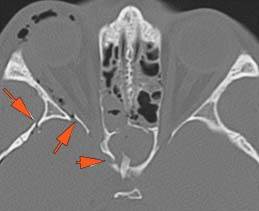

There is bony injury or displacement of the body, angle, ramus, parasymphyseal region, alveolar ridge, and condylar and coronoid process of the mandible. [In case of fracture, describe complexity and displacement].

There is condylar fracture either within or outside of the joint capsule, or with or without involvement of the articular surface of the condylar head.